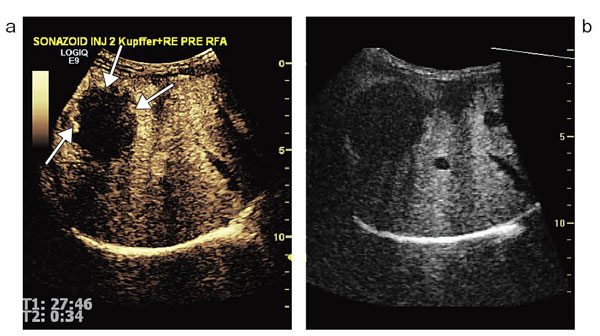

図3 症例2:胆嚢近傍に発生した小さな肝がん

HIFU治療後のソナゾイド造影超音波画像。振幅変調法によるハーモニックモードでは,高エコーに変化した治療域の造影効果を正しく評価できる。

Fusionでは,CTやMRIなどの過去のボリュームデータとリアルタイムの2Dの超音波画像を同一画面上に表示し,位置合わせをしながら比較読影をすることが可能で,例えば,ソナゾイド造影超音波の治療前のKupffer imageのボリュームデータと現在のRe-injection画像とを並べて表示し,位置合わせをすることで,defect像の中の血流の残存がより正確に確認でき(図4),治療計画や治療の穿刺ガイドに有用である。

図4 Volume NavigationのFusion機能

ソナゾイド造影超音波の治療前のKupffer image(b)と,現在のRe-injection画像(a)。→が残存部位。